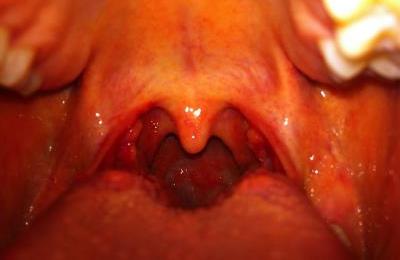

Хронический гипертрофический фарингит, симптомы которого проявляются увеличением слизистой и глоточных миндалин, которое происходит из-за пролиферации лимфоидной ткани из-за длительного хронического воспаления.

Хронический субатрофический фарингит можно назвать переходной формой между типами заболевания. Хронический атрофический фарингит характеризуется уменьшением размеров лимфоузлов из-за развития соединительной ткани в горле.

Катаральный хронический фарингит часто развивается из-за неверного лечения острой формы заболевания. Со временем воспаленные миндалины сами становятся источником инфекции.